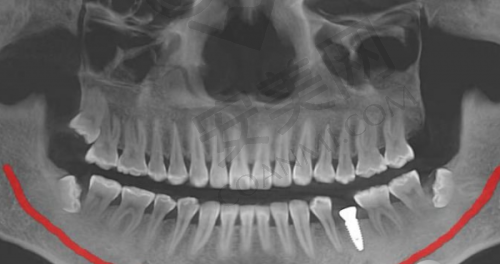

我来到杭州瑞创口腔医院后,首先在前台进行了登记,工作人员热情地接待了我,并引导我到候诊区等待。在候诊区,我看到医院的环境非常整洁、舒适,还提供了免费的茶水和杂志。没过多久,就轮到我就诊了。我见到了为我接诊的医生,医生非常和蔼可亲,他先详细地询问了我的牙齿缺失情况和病史,然后对我的口腔进行了全方面的检查。检查过程中,医生一边操作一边向我解释每一个步骤,让我对自己的口腔情况有了更清楚的了解。之后,医生安排我去做了口腔CT检查,通过CT影像,医生能够更正确地了解我的牙槽骨情况,为制定种植方案提供依据。

做完CT检查后,医生根据我的口腔检查结果和CT影像,为我制定了个性化的种植方案。医生向我详细地介绍了种植方案的内容,包括种植体的选择、种植的位置和数量等。他告诉我,根据我的牙槽骨情况,选择了适合我的种植体品牌和型号,这种种植体具有良好的生物相容性和稳定性,能够更好地与牙槽骨结合。同时,医生还考虑到了我的美观和功能需求,对种植的位置和角度进行了严谨的设计。在制定方案的过程中,医生还耐心地解答了我提出的各种疑问,让我对种植方案有了充分的了解和信心。

杭州瑞创口腔医院的种植牙技术有特别多特色。首先,医院采用了数字化种植技术,通过口腔CT和计算机辅助设计,能够更严谨地规划种植位置和角度,提高种植的成功几率。其次,医院拥有多种品牌和型号的种植体可供选择,医生会根据患者的具体情况,为患者推荐更适合的种植体,确保种植成效和使用寿命。此外,医院的医生团队经验多,他们在种植牙领域有着深厚的造诣,能够为患者提供个性化的治疗方案。而且医院的服务也非常贴心,从就诊前的询问到术后的回访,每一个环节都让患者感受到了关怀和温暖。